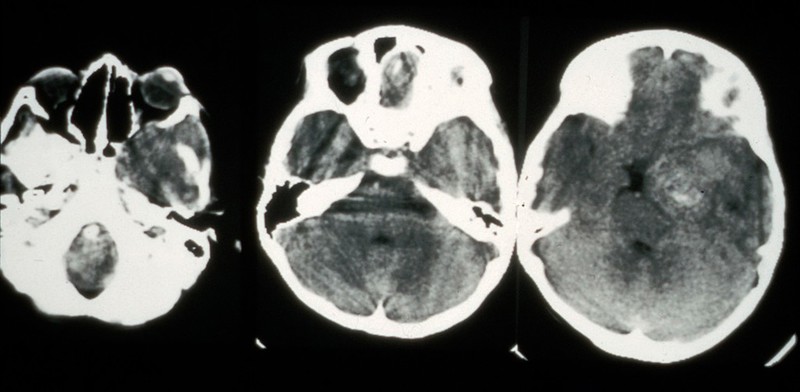

Rhabdomyosarcoma

neuroradiologyteachingfiles.com

neuroradiologyteachingfiles.com

rhabdomyosarcoma